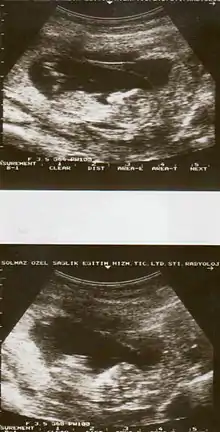

The cause of placental abruption is not entirely clear.[2] Risk factors include smoking, pre-eclampsia, prior abruption (most important and predictive risk factor), trauma during pregnancy, cocaine use, and previous cesarean section.[2][1] Diagnosis is based on symptoms and supported by ultrasound.[1] It is classified as a complication of pregnancy.[1]

Placental abruption is suspected when a pregnant mother has sudden localized abdominal pain with or without bleeding. The fundus may be monitored because a rising fundus can indicate bleeding. An ultrasound may be used to rule out placenta praevia but is not diagnostic for abruption.[8] The diagnosis is one of exclusion, meaning other possible sources of vaginal bleeding or abdominal pain have to be ruled out in order to diagnose placental abruption.[5] Of note, use of magnetic resonance imaging has been found to be highly sensitive in depicting placental abruption, and may be considered if no ultrasound evidence of placental abruption is present, especially if the diagnosis of placental abruption would change management.[16]